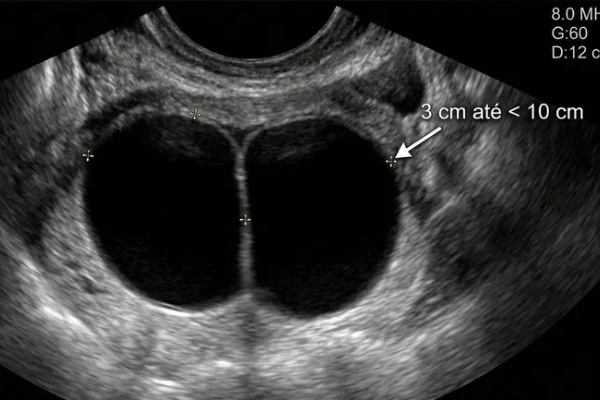

O-RADS US 3 — Low Risk of Malignancy

Risk: <10%Typically benign ovarian lesions ≥10 cm and other low-risk findings (large smooth cysts, irregular inner wall <3 mm, multilocular <10 cm with smooth wall, solid lesions with smooth surface).

Other lesions

If not surgically removed, consider follow-up US at 6 months. In some scenarios, shorter imaging follow-up may be considered (e.g., clinical factors). During follow-up: • If smaller (≥10–15% decrease in average linear dimension), no further surveillance. • If stable, follow-up US at 24 months from the initial exam. • If enlarging (≥10–15% increase in average linear dimension), consider follow-up US at 12 and 24 months from the initial exam, then manage per gynecology. • For changing morphology, reassess using lexicon descriptors. • Clinical management with gynecology as needed. • For solid lesions, consider specialist US (if available) or MRI (with O-RADS MRI score).